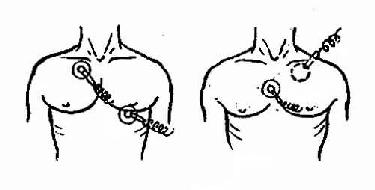

(6)将电极板涂 好导电膏或包上蘸有生理盐水的纱布。将一电极板置于病人胸骨右缘第2、3肋间,另一个置于心尖部。电极板须全部与皮肤紧贴。

胸外电击除颤电极板位置

(7)嘱其他人离开病人床边。术者两臂伸直固定电极板,使自己身体离开床缘,然后双手同时按下放电按钮,进行除颤。